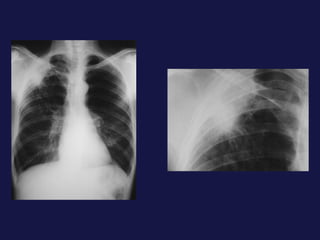

Carcinoma epidermoide ( 30% ). Bronquios centrales, ayuda la citología de esputo. Localización central. Provoca obstrucción bronquial con atelectasia o neumonía postobstructiva sin perdida de volumen mucha cavitación con paredes gruesas e irregulares. 40% lesión periférica,   con bordes espiculados o lobulados. Causa frecuente de pancoast-Tobías.

Carcinoma epidermoide (30% ). Bronquios centrales, ayuda la citología de esputo. Localización central. Provoca obstrucción bronquial con atelectasia o neumonía postobstructiva sin perdida de volumen mucha cavitación con paredes gruesas e irregulares. 40% lesión periférica, con bordes espiculados o lobulados. Causa frecuente de pancoast-Tobías.